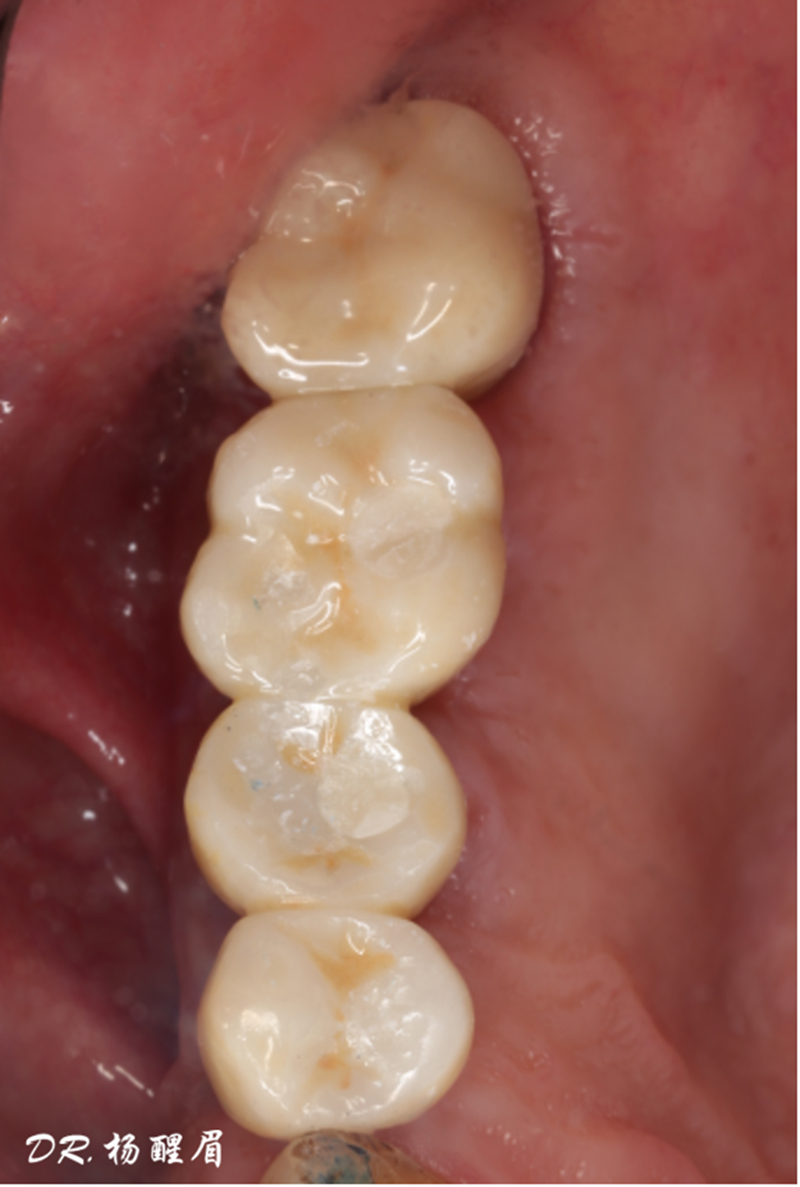

®多顆植體位點及角度的精確性,確保后期修復方案順利完成,也使患者能在使用過程中承受最佳的咬合力

修復完成